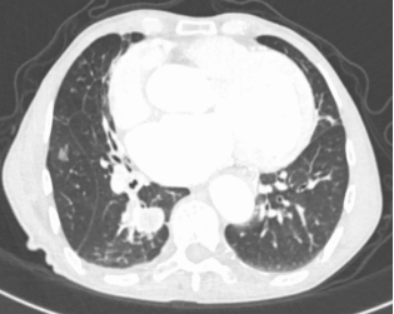

2021-12-26行胸部CT、支气管动脉成像:

1、双肺炎变,右肺上叶空洞形成,考虑继发性肺结核伴空洞形成可能。

2、右肺上叶支气管扩张。

3、右肺上叶支气管动脉增迂曲;主动脉钙化。

入院经积极药物止血治疗后患者仍反复咯血,考虑支气管动脉畸形所致出血,于2021-12-28在局麻下行支气管动脉造影、栓塞术,术后未再咯血,效果良好。